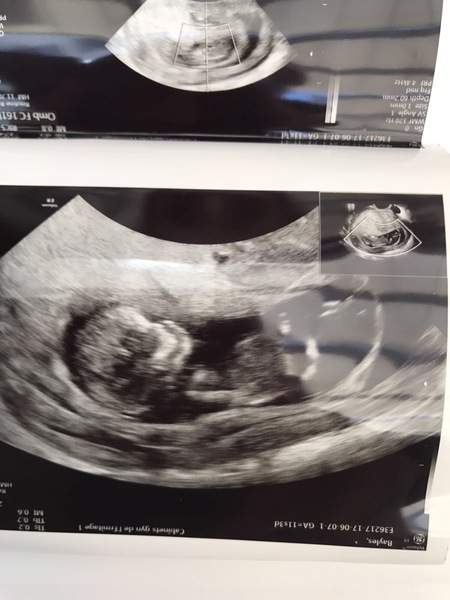

Here is my scan pic, I posted a wee update earlier but it doesn't seem to have gone up.

Everything looks fine thank goodness!

He did say there was quite a bit of brown discharge but could not find any cause apart from a very low-lying placenta.

So unbelievably relieved.

Also had lots of blood taken and felt a bit wobbly so DH took me for a steak and chips lunch afterwards!

Congrats Lapin - lovely scan pic, glad it went well.